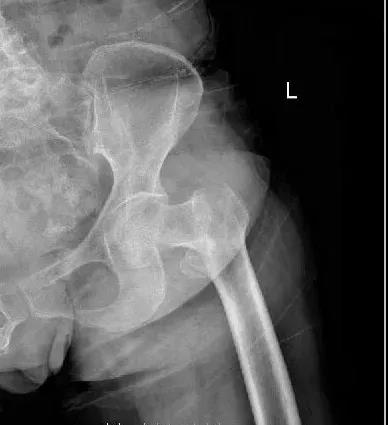

濰坊市濰城區(qū)的高大娘6年前行腦瘤手術(shù),術(shù)后反復(fù)癲癇發(fā)作,遺留了左側(cè)肢體活動(dòng)不靈活的后遺癥,并且有房顫病史5年,近日凌晨起床去廁所時(shí)不慎摔倒,當(dāng)即感到左髖部疼痛明顯,不能站立及行走,在家休息后未見(jiàn)明顯好轉(zhuǎn),家人遂將高大娘送到我院做診治,經(jīng)過(guò)骨科副主任孫守全查體考慮為老年人常見(jiàn)的髖部骨折,遂給于髖部拍片檢查示:左側(cè)股骨粗隆間粉碎性骨折。

考慮這類(lèi)骨折的特點(diǎn),孫主任為高大娘及家屬進(jìn)行了詳細(xì)的解釋?zhuān)⒔ㄗh收住院行手術(shù)治療,高大娘住到了我院的骨科病房,在孫主任帶領(lǐng)下骨科醫(yī)務(wù)人員為高大娘做了詳細(xì)的病情討論。因?yàn)楦叽竽锿心X瘤手術(shù)史,癲癇、高血壓病、心房纖顫等內(nèi)科基礎(chǔ)病史,院外服用多種藥物治療,平素左側(cè)肢體活動(dòng)不靈活,考慮病人的個(gè)體因素及年齡,決定為步大娘做PFNA內(nèi)固定術(shù),減少手術(shù)時(shí)間,縮短臥床時(shí)間,盡早下地活動(dòng),提高生活質(zhì)量。在麻醉科、心內(nèi)科多學(xué)科的協(xié)助下,經(jīng)過(guò)周密的術(shù)前準(zhǔn)備,排除明顯手術(shù)禁忌,我院骨科團(tuán)隊(duì)為高大娘順利完成左股骨粗隆間粉碎性骨折閉合復(fù)位PFNA內(nèi)固定術(shù),病人術(shù)后3天就可以在保護(hù)下下地活動(dòng)了,病人的快速康復(fù)不僅給病人帶來(lái)了生活的信心,也大大解決了家人護(hù)理的麻煩,高大娘及家屬對(duì)我院骨科的治療方案及治療結(jié)果非常滿(mǎn)意。